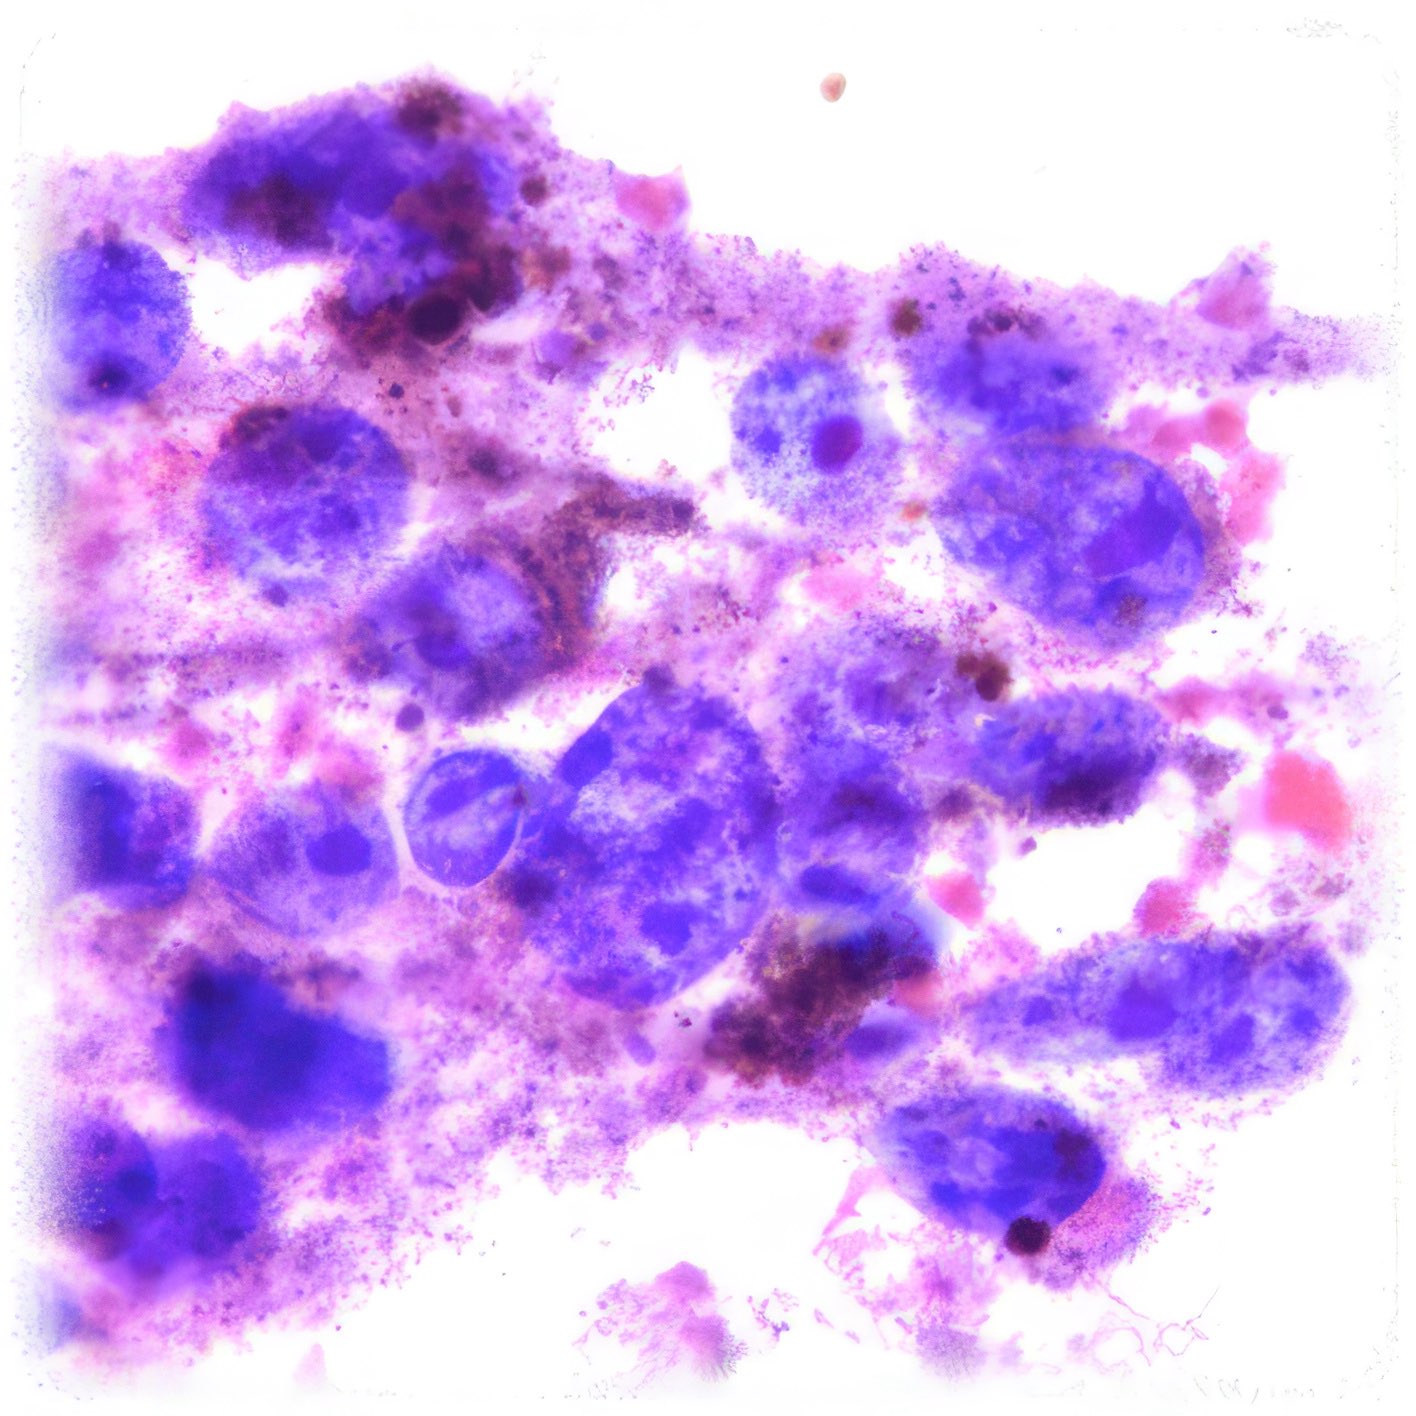

(Abbildungen 3 - 6: Pap, Vergrößerung 1000x)

Beschreibung

Makroskopisch zeigt die areoläre Haut (Brustwarzenhof) eine feine ekzemartige nässende granuläre Struktur; die Brustwarze ist nicht eingezogen (Abb. 1 und 2). Die extrem atypischen Zellen liegen verstreut (Abb. 3), oder bilden lose zusammenhängende Gruppen (Abb. 4, 6). Einige sind doppelkernig. Im Vergleich zum gewöhnlichen Mammakarzinom sind sie extrem pleomorph und ihre Kerne sind stärker hyperchromatisch, sehr grob strukturiert, und zeigen manchmal prominente Chromozentren. Das Zytoplasma ist unterschiedlich breit und erscheint manchmal als vakuolär.